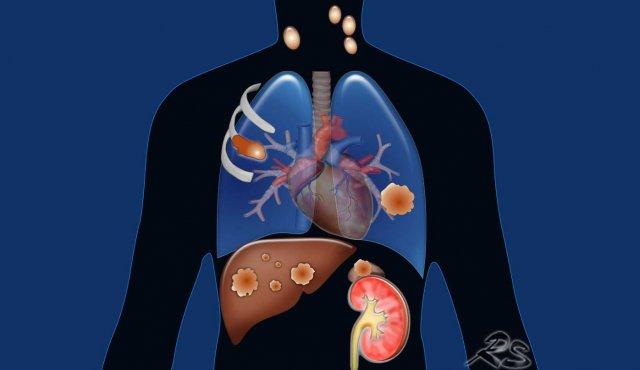

Phân giai đoạn M dựa trên sự hiện diện của các di căn, vị trí và tính đa ổ của chúng.

M0 là không có di căn và M1 có nghĩa là di căn xa.

Cần phân biệt giữa bệnh di căn tại vùng hoặc trong lồng ngực (M1a) và bệnh di căn xa, có thể là đơn độc (M1b) hoặc đa ổ (M1c), trong một hệ cơ quan đơn lẻ (M1c1) hoặc trong nhiều cơ quan (M1c2).

M1a: Bệnh di căn tại vùng (hoặc trong lồng ngực) được định nghĩa là tràn dịch màng phổi hoặc màng ngoài tim ác tính hoặc các nốt, cũng như các nốt phổi riêng biệt ở phía đối bên.

M1b là một tổn thương di căn ngoài lồng ngực đơn độc trong một hệ cơ quan đơn lẻ. Cần nhấn mạnh rằng, một hệ cơ quan bao gồm tất cả các vị trí của hệ cơ quan đó phân bố khắp cơ thể, hoặc cả hai bên trong trường hợp cơ quan đôi.

Điều này có nghĩa là nhiều tổn thương ở các vị trí khác nhau của hệ xương hoặc da là bệnh M1c1.

Tuy nhiên,

nhiều tổn thương ở cả hệ xương và tuyến thượng thận là bệnh M1c2.

Hình minh họa

M1b: Di căn ngoài lồng ngực đơn độc trong một hệ cơ quan đơn lẻ.

Có thể là ở một hạch bạch huyết ngoài vùng (không kèm di căn gan) hoặc một tổn thương di căn đơn độc ở gan (không kèm hạch bạch huyết ngoài vùng).

M1c1: Nhiều tổn thương di căn ngoài lồng ngực trong một cơ quan đơn lẻ.

Hầu hết các cơ quan đều có thể bị ảnh hưởng trong bệnh di căn.

Di căn thường gặp ở tuyến thượng thận, hạch bạch huyết, não, xương và gan.

M1c2: Nhiều tổn thương di căn ngoài lồng ngực trong nhiều hệ cơ quan.